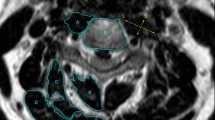

All enrolled patients underwent a preoperative 3.0 T MRI scan using Siemens Medical Solutions equipment in Erlangen, Germany. Axial MRI images were aligned parallel to the inferior endplate of the vertebral body. The cross-sectional area (CSA) of the vertebral body served as a reference point. CSA at each level was calculated by outlining a polygon shape around the outer margins of fat tissue, extensor muscles, and the vertebral body on axial T2-weighted images. ImageJ was utilized for measurements, distinguishing functional muscle (without fatty infiltration) using the software's threshold. The measurement protocol focused on the fan-shaped region enclosed by lines connecting the midpoint of the anterior vertebral body and the front vertices of the sides of the vertebrae. Extensor muscles, including multifidus, rotators, semispinalis capitis and cervicis, splenius capitis and cervicis, levator scapulae, and longissimus, were included in the assessment. CSA ratios between fat, muscle, and centrum were also measured.

Table 1 and Fig. 3 elaborate on the methods used to measure cervical MRI parameters. In cases of multisegment degeneration, measurement focused on the most severe segment.

The measurement range is within the fan shape enclosed by the bilateral lines connecting the midpoint of the anterior vertebral body and the front vertices of the side blocks. A, Vertebral body; B, Multifidus; C, Semispinalis cervicis; D, Semispinalis capitis; E, Splenius capitis and cervicis; F, Levator scapulae and Longissimus; G, Fat; Muscle area = B + C + D + E + F. Fat area = G + Fat infiltration in the muscle area.